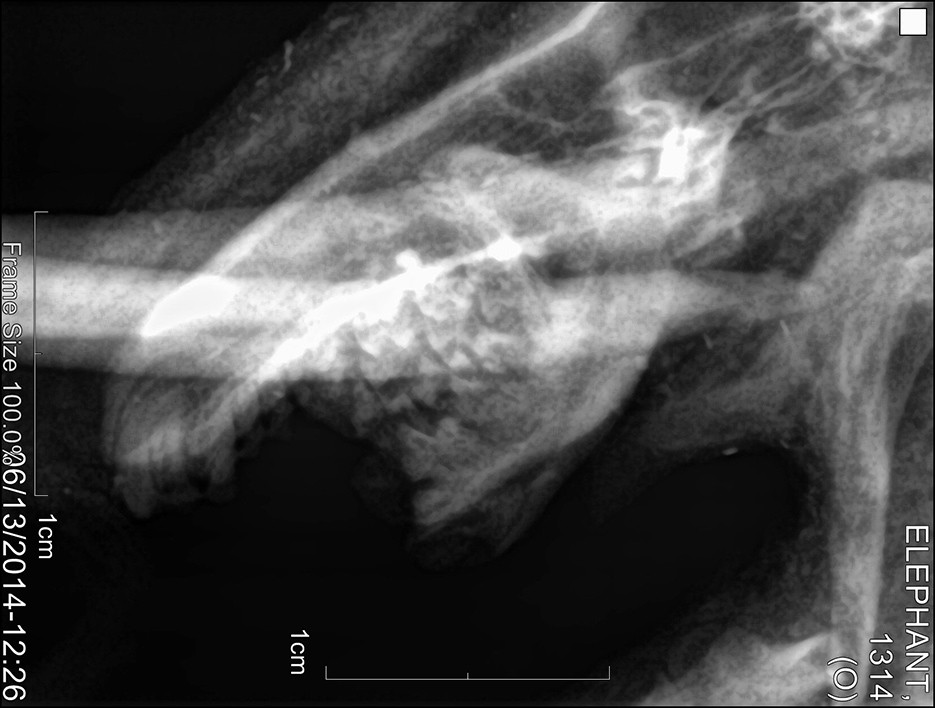

Der von ihm geforderte Beweis scheint inzwischen zumindest teilweise erbracht zu sein. Wissenschaftler und Forscher des Pha Woh Hospitals im Mae Sot Distrikt haben Überreste solcher Wasserelefanten untersucht. Die Röntgenaufnahmen der kleinen Körper zeigen, daß diese winzigen Wesen eine Knochenstruktur haben, welche jener der ausgewachsenen asiatischen Elefanten gleicht.

Röntgen1 Röntgen2 Röntgen3

(Original-Röntgenaufnahmen des untersuchten Exemplars)